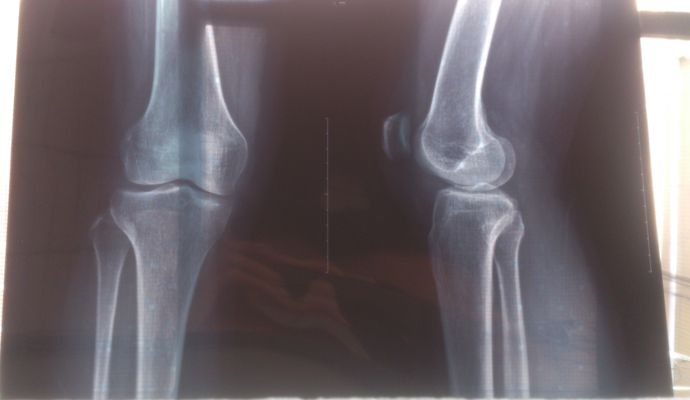

膝盖是由股骨下端,胫骨上端及膑骨所组成,外包以关节囊,内有交叉韧带及半月板,是人体中最复杂及关节面最大的负重关节。膝关节骨质增生也称为增生性退行性关节炎。

那些治疗骨质增生药物,真的无效的,构成跟身体其他的骨骼是一样的,如果真的可以消灭,那么身体其他的骨质也会消融。但这有可能吗?”拍片说是骨刺,其实那只是对这个不了解,不会长得跟一根刺一样,一般是在韧带,肌腱,肌肉的附着处才会长,所以一般是围绕着骨骼结构长的,像通过手术切掉,那整个骨头都要切一圈,而且,只要再过度使用,就会再长出来。”不是一根刺,是各种各样的形状的,例如一个腰椎,看X 光片,像是刺,其实,整个椎体的边缘都是。”

“有人说,我腰痛,膝盖痛,拍片只有骨质增生,没其他问题啊?其实,那是你们对人体还不了解,拍片有局限性,只能看见骨骼,其他的韧带,肌腱,滑膜,关节囊,半月板,肌肉都看不见,但他们也是可以生病的,看不见的病引起的疼痛。